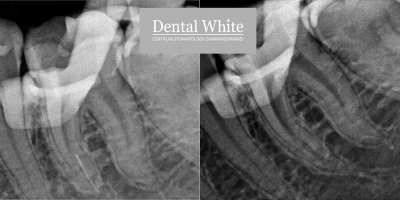

PRZYKŁADY LECZENIA KANAŁOWEGO WYKONANEGO PRZEZ NASZ ZESPÓŁ

Przykłady odstępstw anatomicznych kanałów zębowych